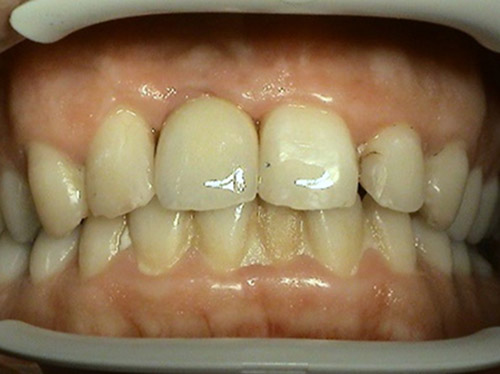

– positive aesthetic effect on facial expression,

charming

and new smile provides better quality of life and restoration of

self-confidence not only

in private life, but also on social and professional level